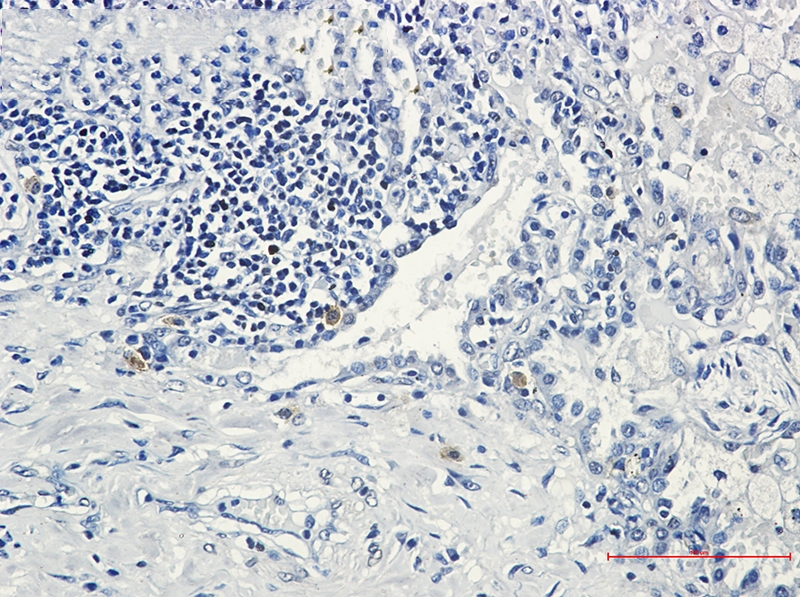

Immunohistochemistry of STK3 in paraffin-embedded Human lung cancer tissue using STK3 Rabbit mAb at dilution 1/50